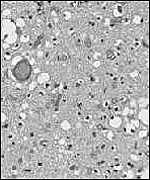

Creutzfeldt-Jakob Disease (“CJD”) is a rare, fatal brain disorder which causes a rapid, progressive dementia and associated neuromuscular disturbances

There had been much debate on the cause of the disease. Now it is accepted that that a transmissible agent is responsible for causing Creutzfeldt-Jakob Disease, as shown by experiments involving the injection of CJD-affected brains into the normal brains of healthy animals. The identification of this transmissible agent has been the subject of much scientific inquiry and debate.

Prion

The agent responsible is either a slow virus or Prion.